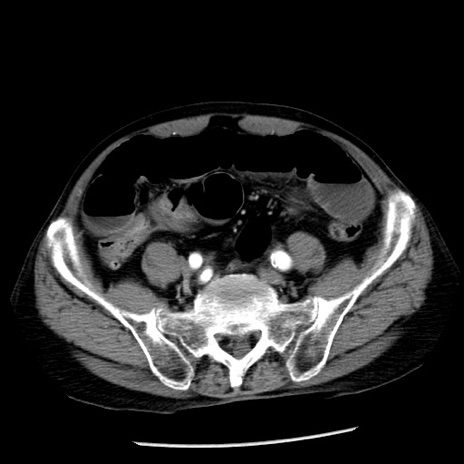

症例26(横断像)

【症例】80歳代男性

【主訴】嘔吐

【現病歴】昨晩2回嘔吐あり、今朝になっても嘔吐あり。来院。

【既往歴】胃潰瘍

【身体所見】意識清明、BT 37.6℃、BP 166/95mmHg、HR 100bpm、SpO2 97%、腹部:平坦・軟、腸蠕動音聴取良好、圧痛なし。

【データ】WBC 21900、CRP 1.46